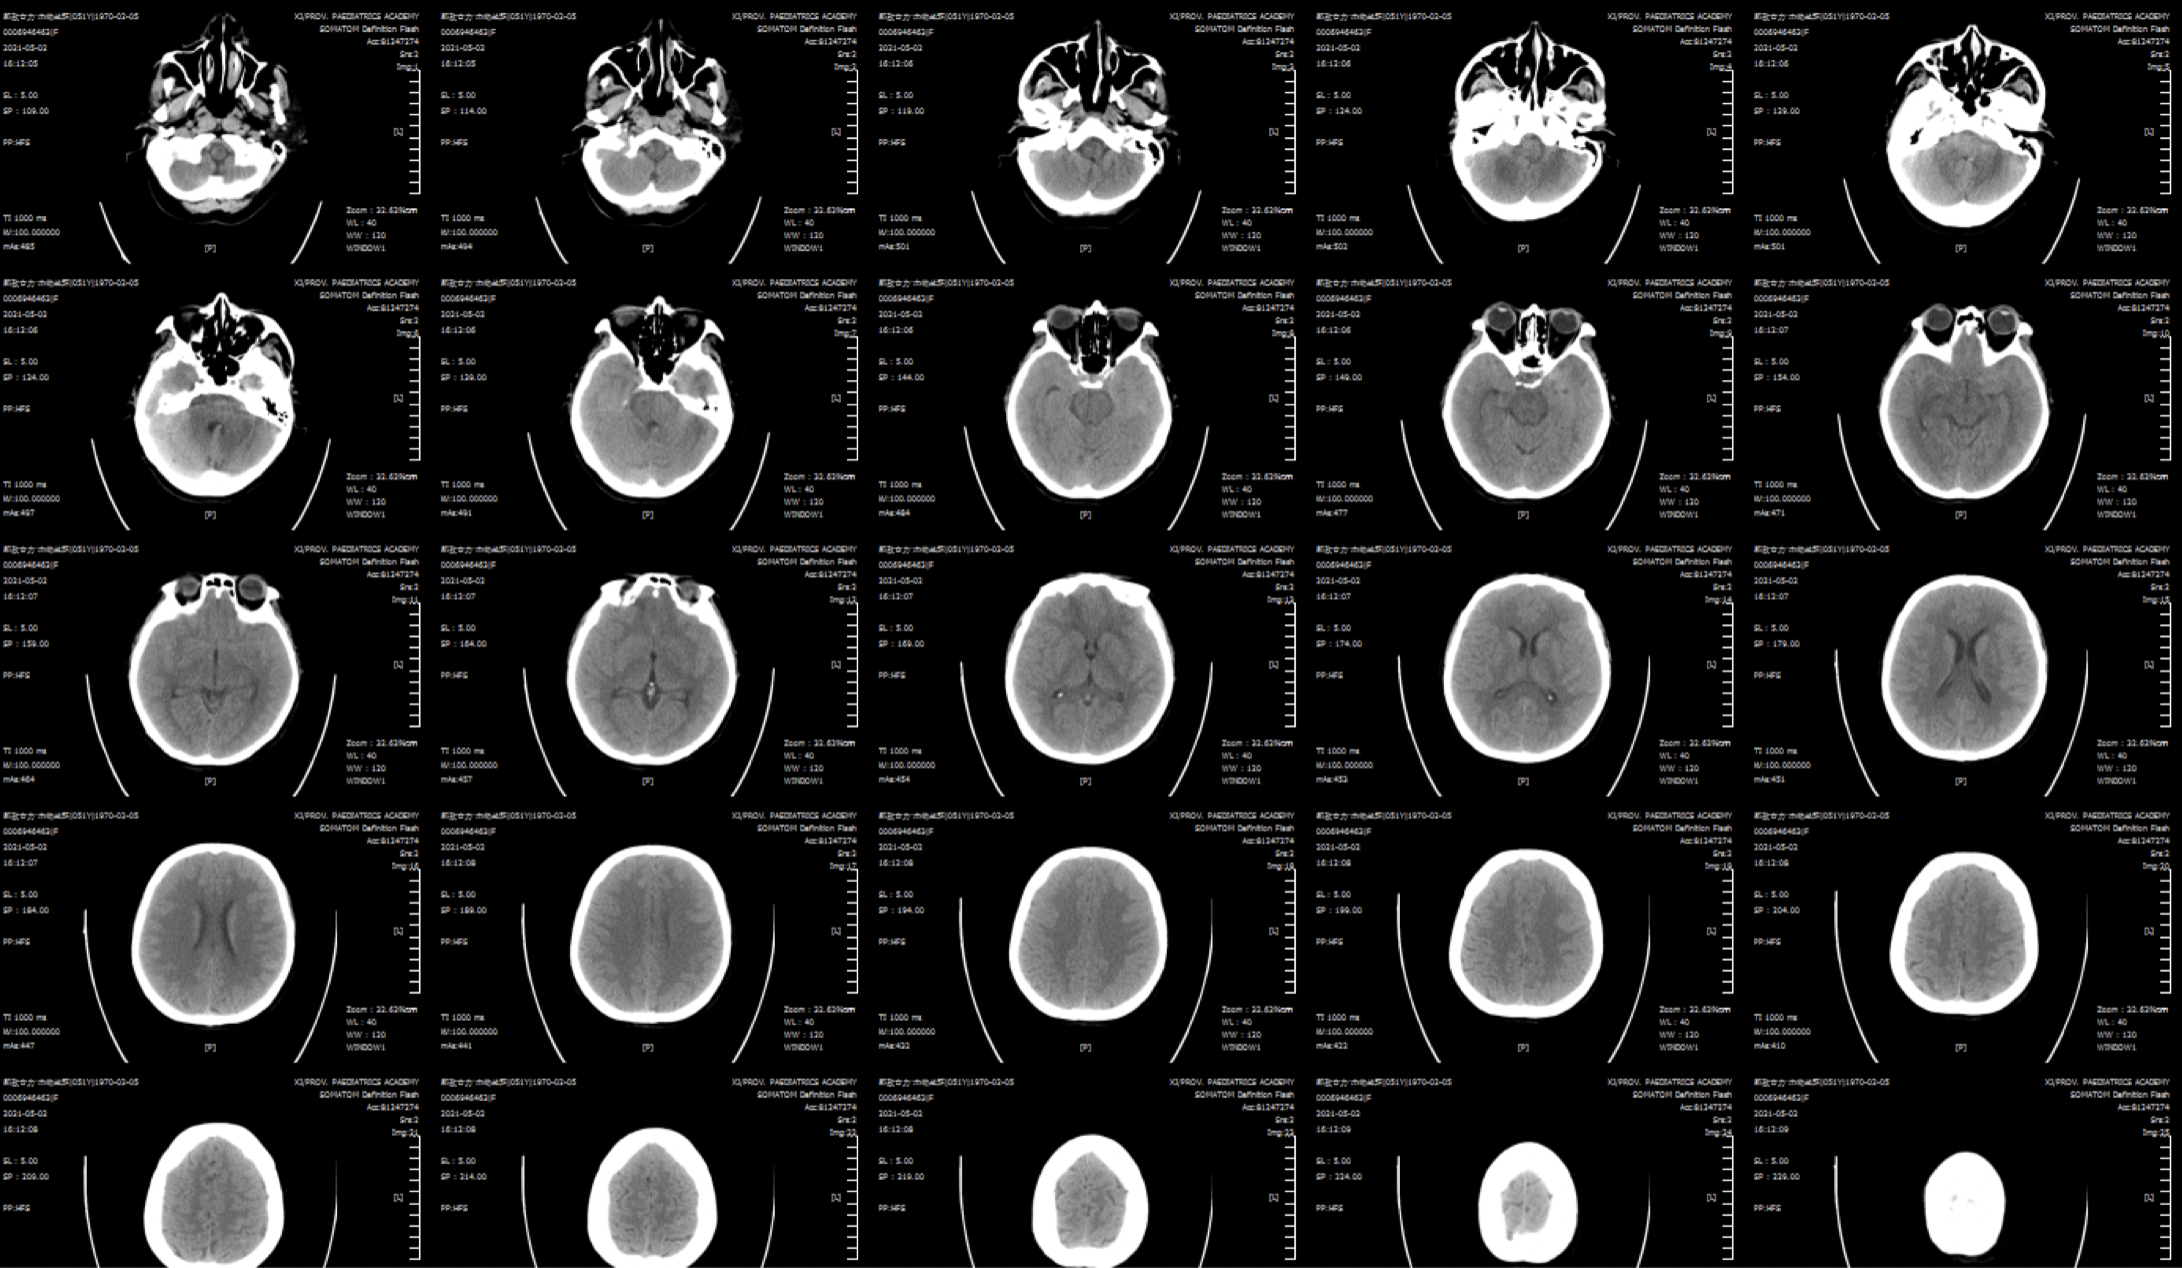

患者,女性,51岁,哈萨克族,以“突发剧烈头痛伴恶心、呕吐2天”收住。在当地发病后就诊当地医院行头颅CTA:双侧颈内动脉颅内段动脉瘤,转入我院。神经系统查体:未见明显阳性体征。外院头颅CT:自发性蛛网膜下腔出血。头颅CTA:颅内多发动脉瘤(未带影像资料)。

入院复查头颅CT:蛛网膜下腔少量出血!